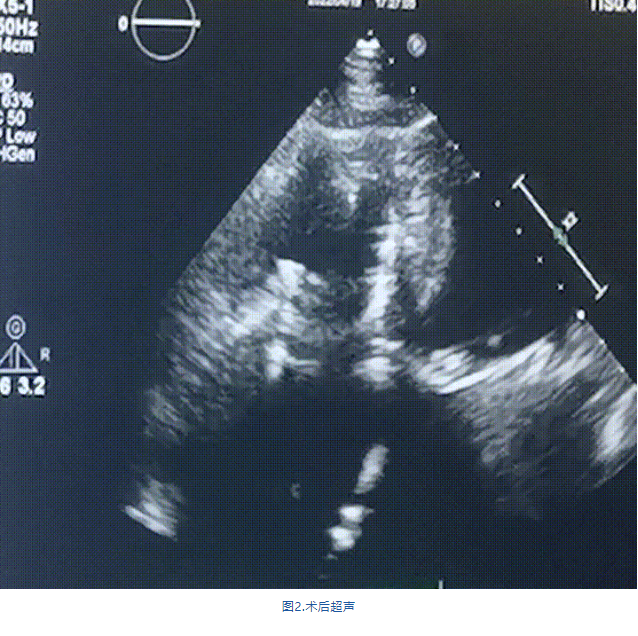

此次手術在全麻下進行,采用經右側頸靜脈入路。術中在經食道超聲和DSA的指引下多個維度精細調整輸送器角度,在達到正確位置后,逐步釋放瓣膜錨定裝置和盤片,最終完成瓣膜植入。術后患者右房壓明顯下降,術后超聲提示人工三尖瓣同軸性良好,瓣架固定牢靠,無反流和瓣周漏,血壓術后即刻上升20mmHg左右,手術后監護室順利拔除氣管插管,3天后恢復良好,予以出院。